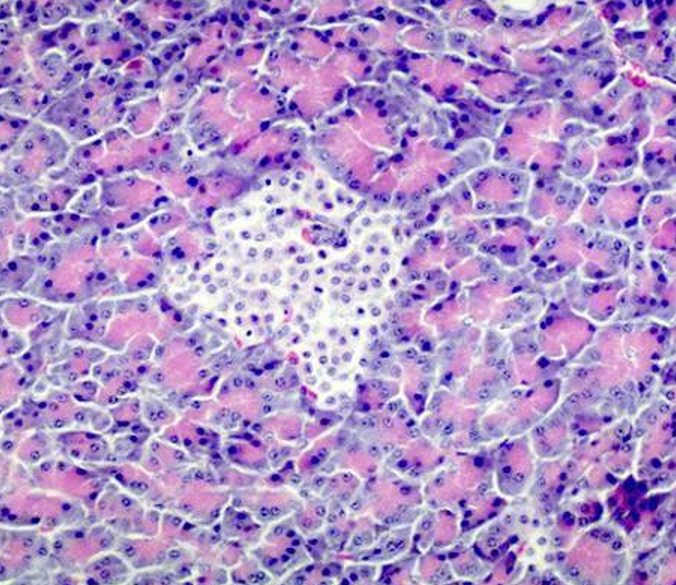

Q

What is this grouping of cells called? Where are they located

A

Islet of Langerhans

Pancreas